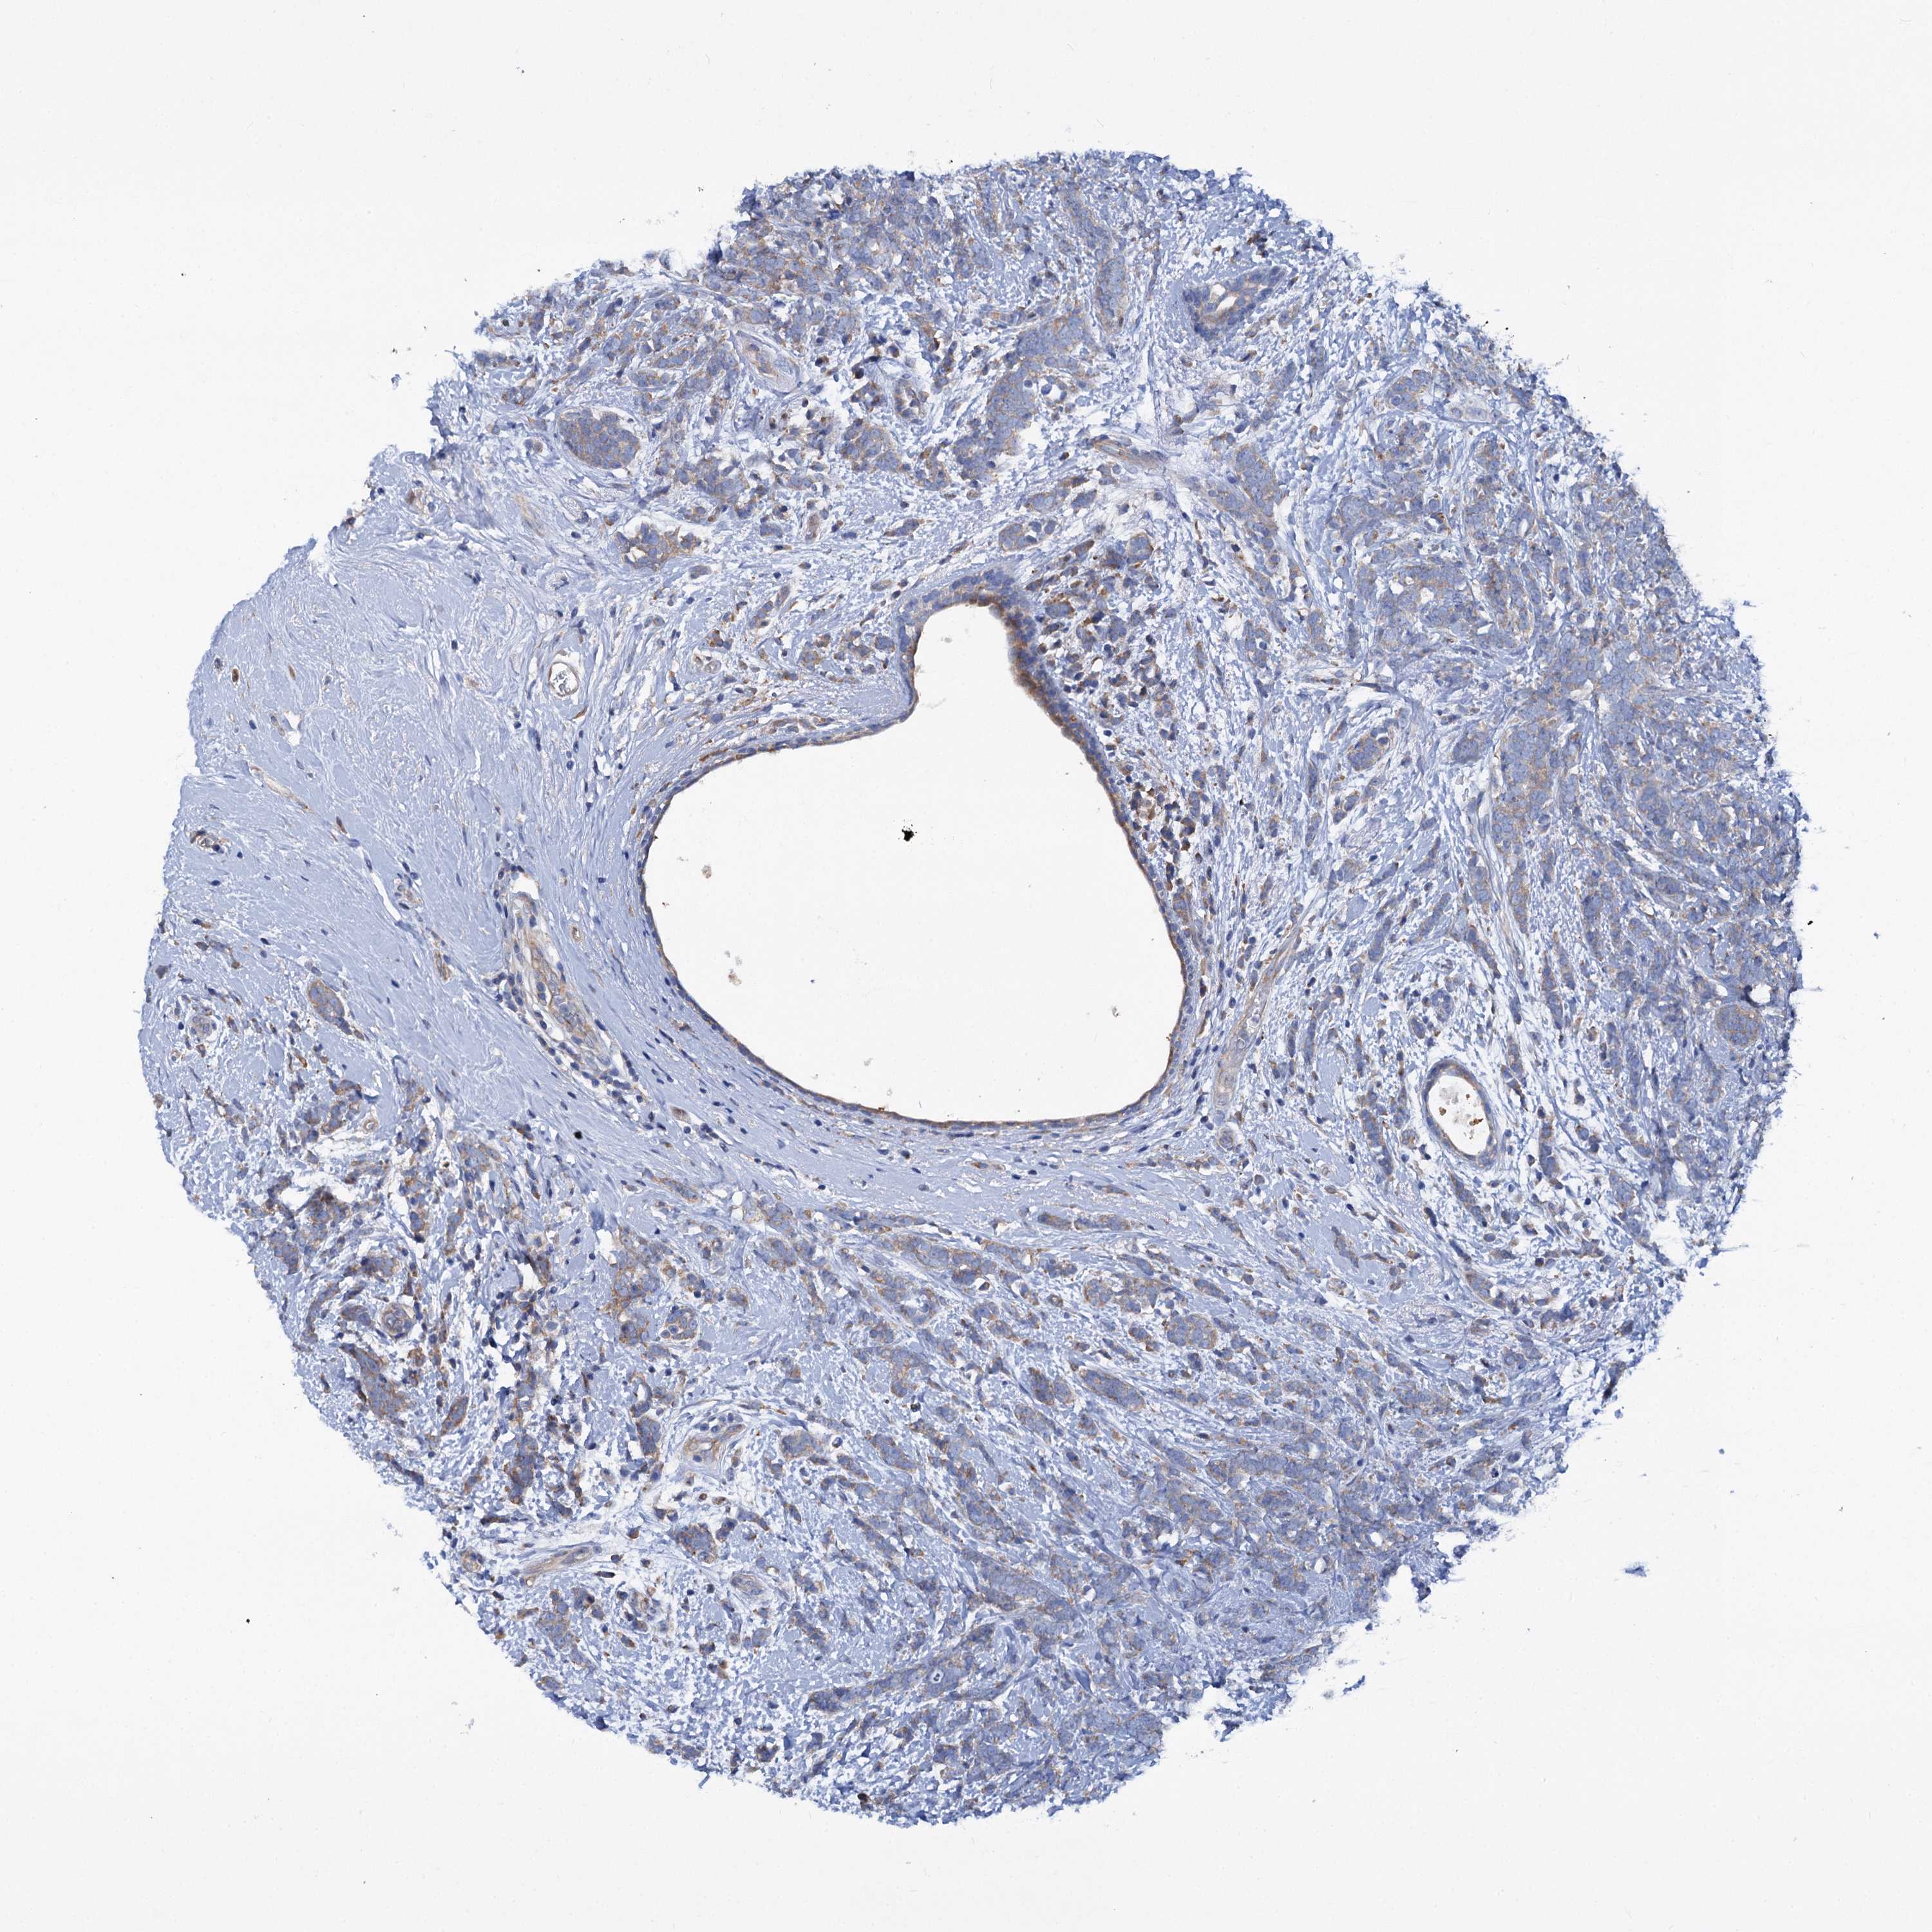

CANCER BREAST CANCER Show tissue menu

BRCA TCGA BRCA VALIDATION PROTEIN EXPRESSION

ANTIBODIES

AND

VALIDATION